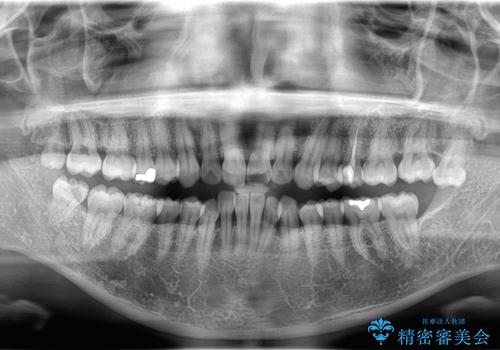

- 「歯のデコボコと前歯が出ているせいで口が閉じにくい」を主訴に来院された患者様です。

上下左右の4番(第一小臼歯)を抜歯をし審美ワイヤー装置で治療を行いました。

抜歯矯正により歯列のデコボコ(叢生)が改善し、前歯の突出も解消されたことで口元が下がり、すっきりとした印象となりました。